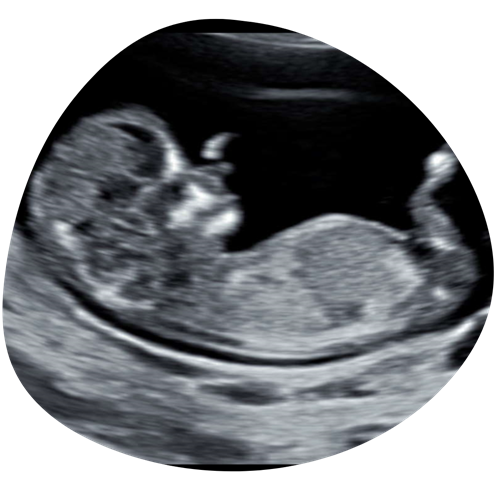

2D echo

Tijdens je hele zwangerschap kunnen we je kindje in 2D laten zien. We kunnen met 2D goed naar de structuren in het lichaampje van je kindje kijken en naar bijvoorbeeld het profieltje, handjes, voetjes etc. Geef vooral aan wat jullie graag willen zien!

€35 (15 minuten)